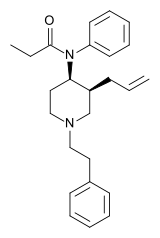

The pharmacodynamic response to an opioid depends upon the receptor to which it binds, its affinity for that receptor, and whether the opioid is an agonist or an antagonist. For example, the supraspinal analgesic properties of the opioid agonist morphine are mediated by activation of the μ1 receptor; respiratory depression and physical dependence by the μ2 receptor; and sedation and spinal analgesia by the κ receptor. Each group of opioid receptors elicits a distinct set of neurological responses, with the receptor subtypes (such as μ1 and μ2 for example) providing even more [measurably] specific responses. Unique to each opioid is its distinct binding affinity to the various classes of opioid receptors (e.g. the μ, κ, and δ opioid receptors are activated at different magnitudes according to the specific receptor binding affinities of the opioid). For example, the opiate alkaloid morphine exhibits high-affinity binding to the μ-opioid receptor, while ketazocine exhibits high affinity to ĸ receptors. It is this combinatorial mechanism that allows for such a wide class of opioids and molecular designs to exist, each with its own unique effect profile. Their individual molecular structure is also responsible for their different duration of action, whereby metabolic breakdown (such as N-dealkylation) is responsible for opioid metabolism.

Anilidopiperidines

Phenylpiperidines